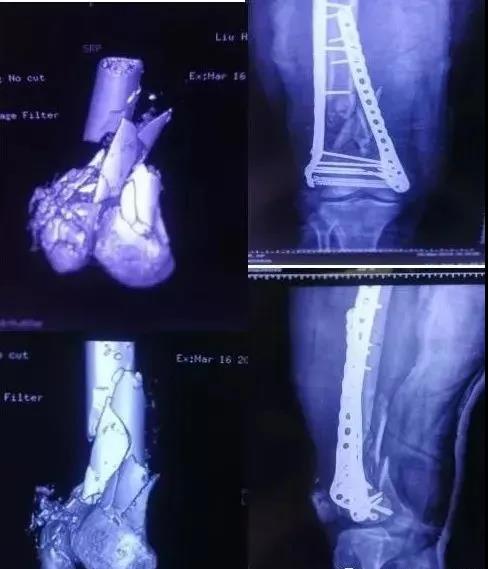

3)股骨远端骨折

- 开放性骨折,伤及腘动脉,坐骨神经,紧急手术,超膝关节外支架。

- 单纯闭合骨折,内固定:钢板或逆行髓内钉。